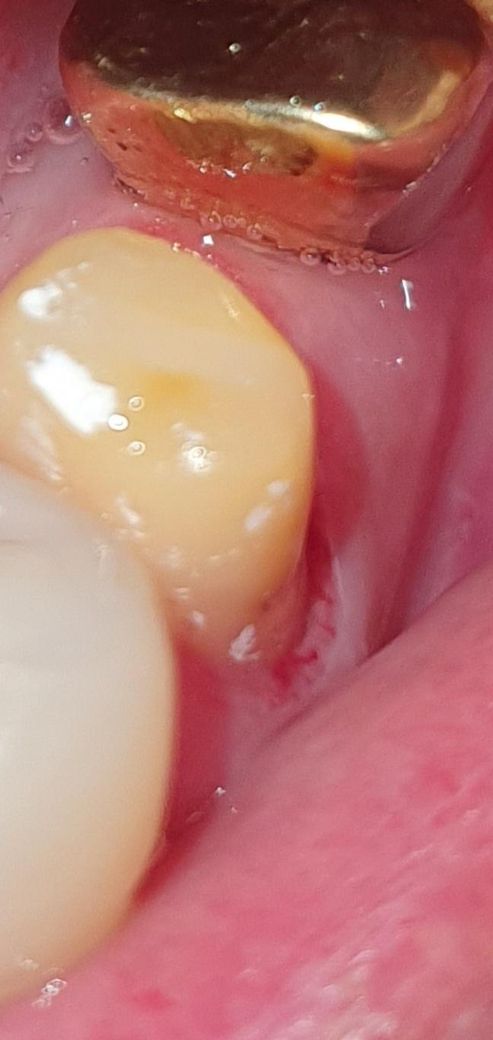

치위생사가 치은절재술을 할수 있는건가요?

치위생사가 치은절재술인지 잇몸을 절재를 했는데 치과에서는 잇몸 절재를 하지않았다고 말하는군요 치위생사가 만일 치은절재술을 해도 되는건가요?

• 1번 째 사진

치과 위생사 선생님은 치은절제술을 할수 없습니다. 치은 절제술은 마취도 필요 하고 다른 기구도 사용해야되서 시술할수 없습니다.

치위생사가 치은절재술인지 잇몸을 절재를 했는데 치과에서는 잇몸 절재를 하지않았다고 말하는군요 치위생사가 만일 치은절재술을 해도 되는건가요? -> 못합니다